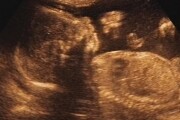

Vypočtěte si v naší těhotenské kalkulačce, kdy Vás čekají ultrazvuky, kdy obdržíte těhotenskou průkazku, kdy se podrobíte triple testu, kdy se vyšetřuje streptokok, kdy se provádí amniocentéza, kdy byste si měla nachystat věci do porodnice, kdy nastupujete mateřskou dovolenou.

Zaregistrujte se na Babyonline.cz, uveďte termín porodu a každý týden vám automaticky přijde e-mail s informacemi o vašem těhotenství týden po týdnu a vývoji miminka!